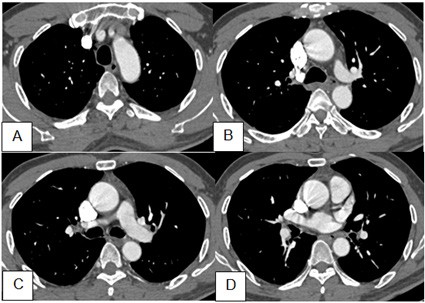

Hình 2. Phim CT ngực bệnh nhân khi vào viện, ảnh dựng MPR ở 3 bình diện. A: Axial; B: Sagital lệch phải; C: Coronal. Nốt bán đặc vị trí phân thuỳ II phổi phải, có dấu hiệu xâm lấn màng phổi tạng.

Hình 3. Cửa ổ trung thất sau tiêm trên 4 lát cắt từ trên xuống: không thấy hạch lớn trung thất, rốn phổi

* Kết luận của CT ngực: Theo dõi nốt đơn độc, dạng bán đặc thuỳ trên phổi phải, nhiều khả năng ác tính.